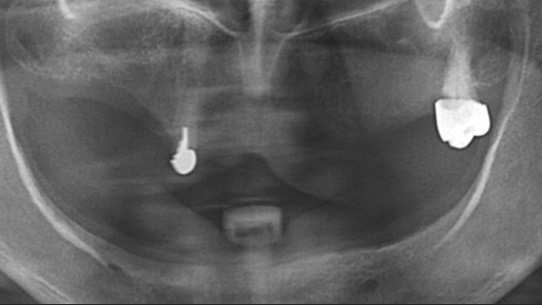

치아상실 상태가 오래 되어 적절한 영양섭취가 힘들어 “영양부족”으로 내원한 환자분. 우선 영양섭취를 위하여 음식물을 씹을 수 있는

임시치아를 빠르게 만들어 드렸습니다. 건강상태가 회복되어 상악은 12개의 임플란트를 식립 하고, 하악의 경우 잇몸 뼈가 많이 소실되어

2개의 임플란트를 식립하고 임플란트 틀니를 장착하였습니다.